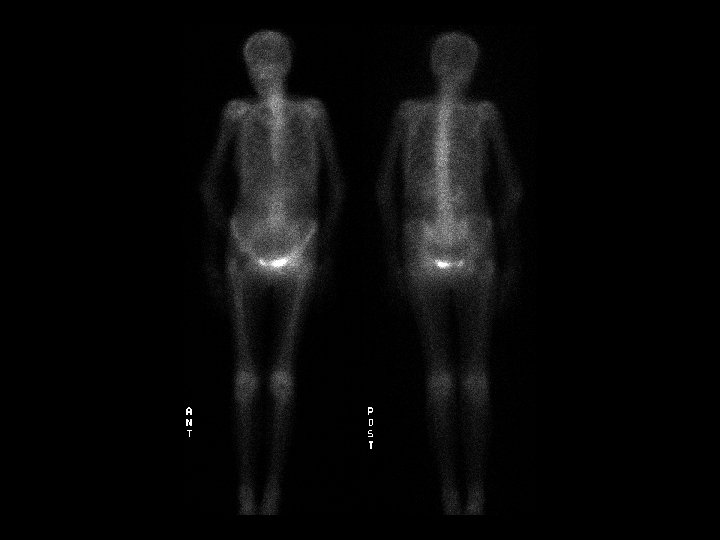

Superscan • • Findings: – Diffusely increased radiotracer activity of the skeleton – No renal or soft tissue uptake ddx: – Diffuse metastates – Metabolic • Renal osteodystrophy